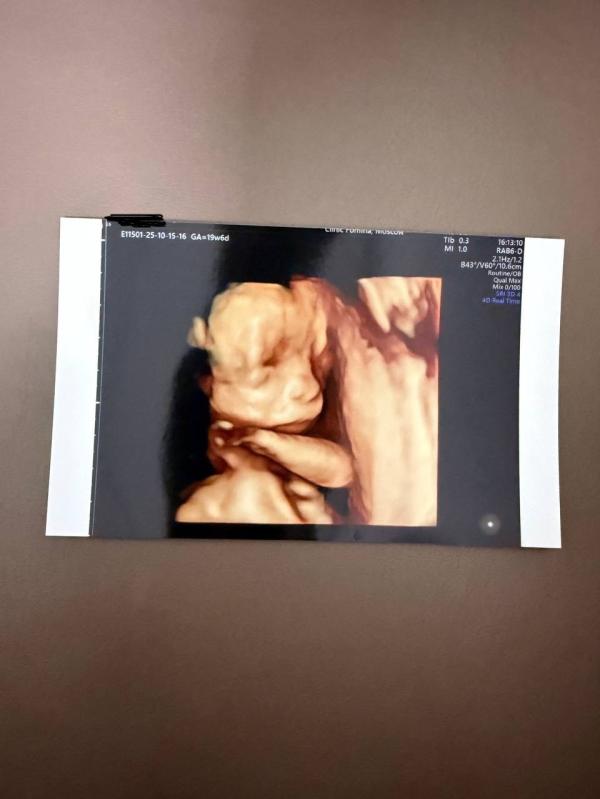

2 скрининг done✔️

Мальчишка растёт не по дням🙃

Уже 383 грамма ⚖️

Все показатели малыша в норме, в том числе и все мои кровотоки.

По сроку вроде ровненько идем, ПДР пока стоит на 5 марта, но я конечно надеюсь что 4 роды случатся как-то пораньше 40 недель.

Ретрохориальная сепарация так никуда и не делась, но стала меньше и организовалась, есть надежда что совсем пропадёт к 24-25 неделе.

В клинике Фомина делали, на фото 3д, но 4д у них тоже возможно сделать.

4д это видео ,записывают на диск